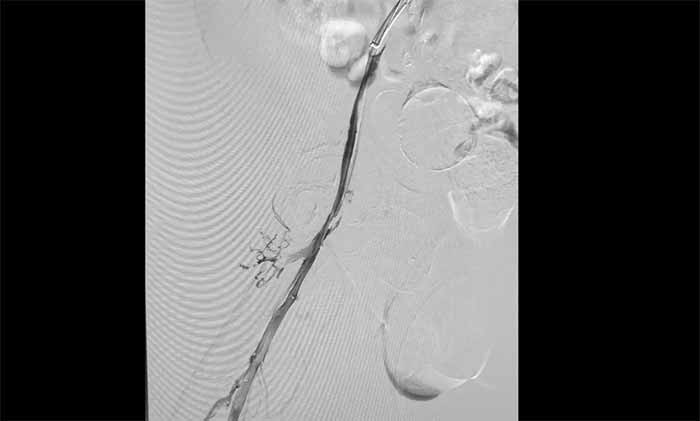

近日,上海蓝十字脑科医院脑血管病科收治了一名脑出血术后长期卧床导致下肢深静脉血栓形成的老年男性患者。患者在外院康复期间发现右下肢严重肿胀,超声提示深静脉血栓,紧急转入本院。

席刚明教授与脑血管病一科4A病区副主任王贵平博士分析指出,下肢深静脉血栓一旦脱落,可随血流引发肺栓塞,危及生命。考虑到患者血栓形成时间较长、抗凝效果不佳,团队决定行介入手术治疗。术后造影显示血栓基本消失,下肢静脉恢复通畅,患者右下肢肿胀明显缓解。

席教授提醒,即便置入滤器,仍需规范抗凝治疗,以预防新血栓形成并降低脱落风险。

▲ 取出大量血栓